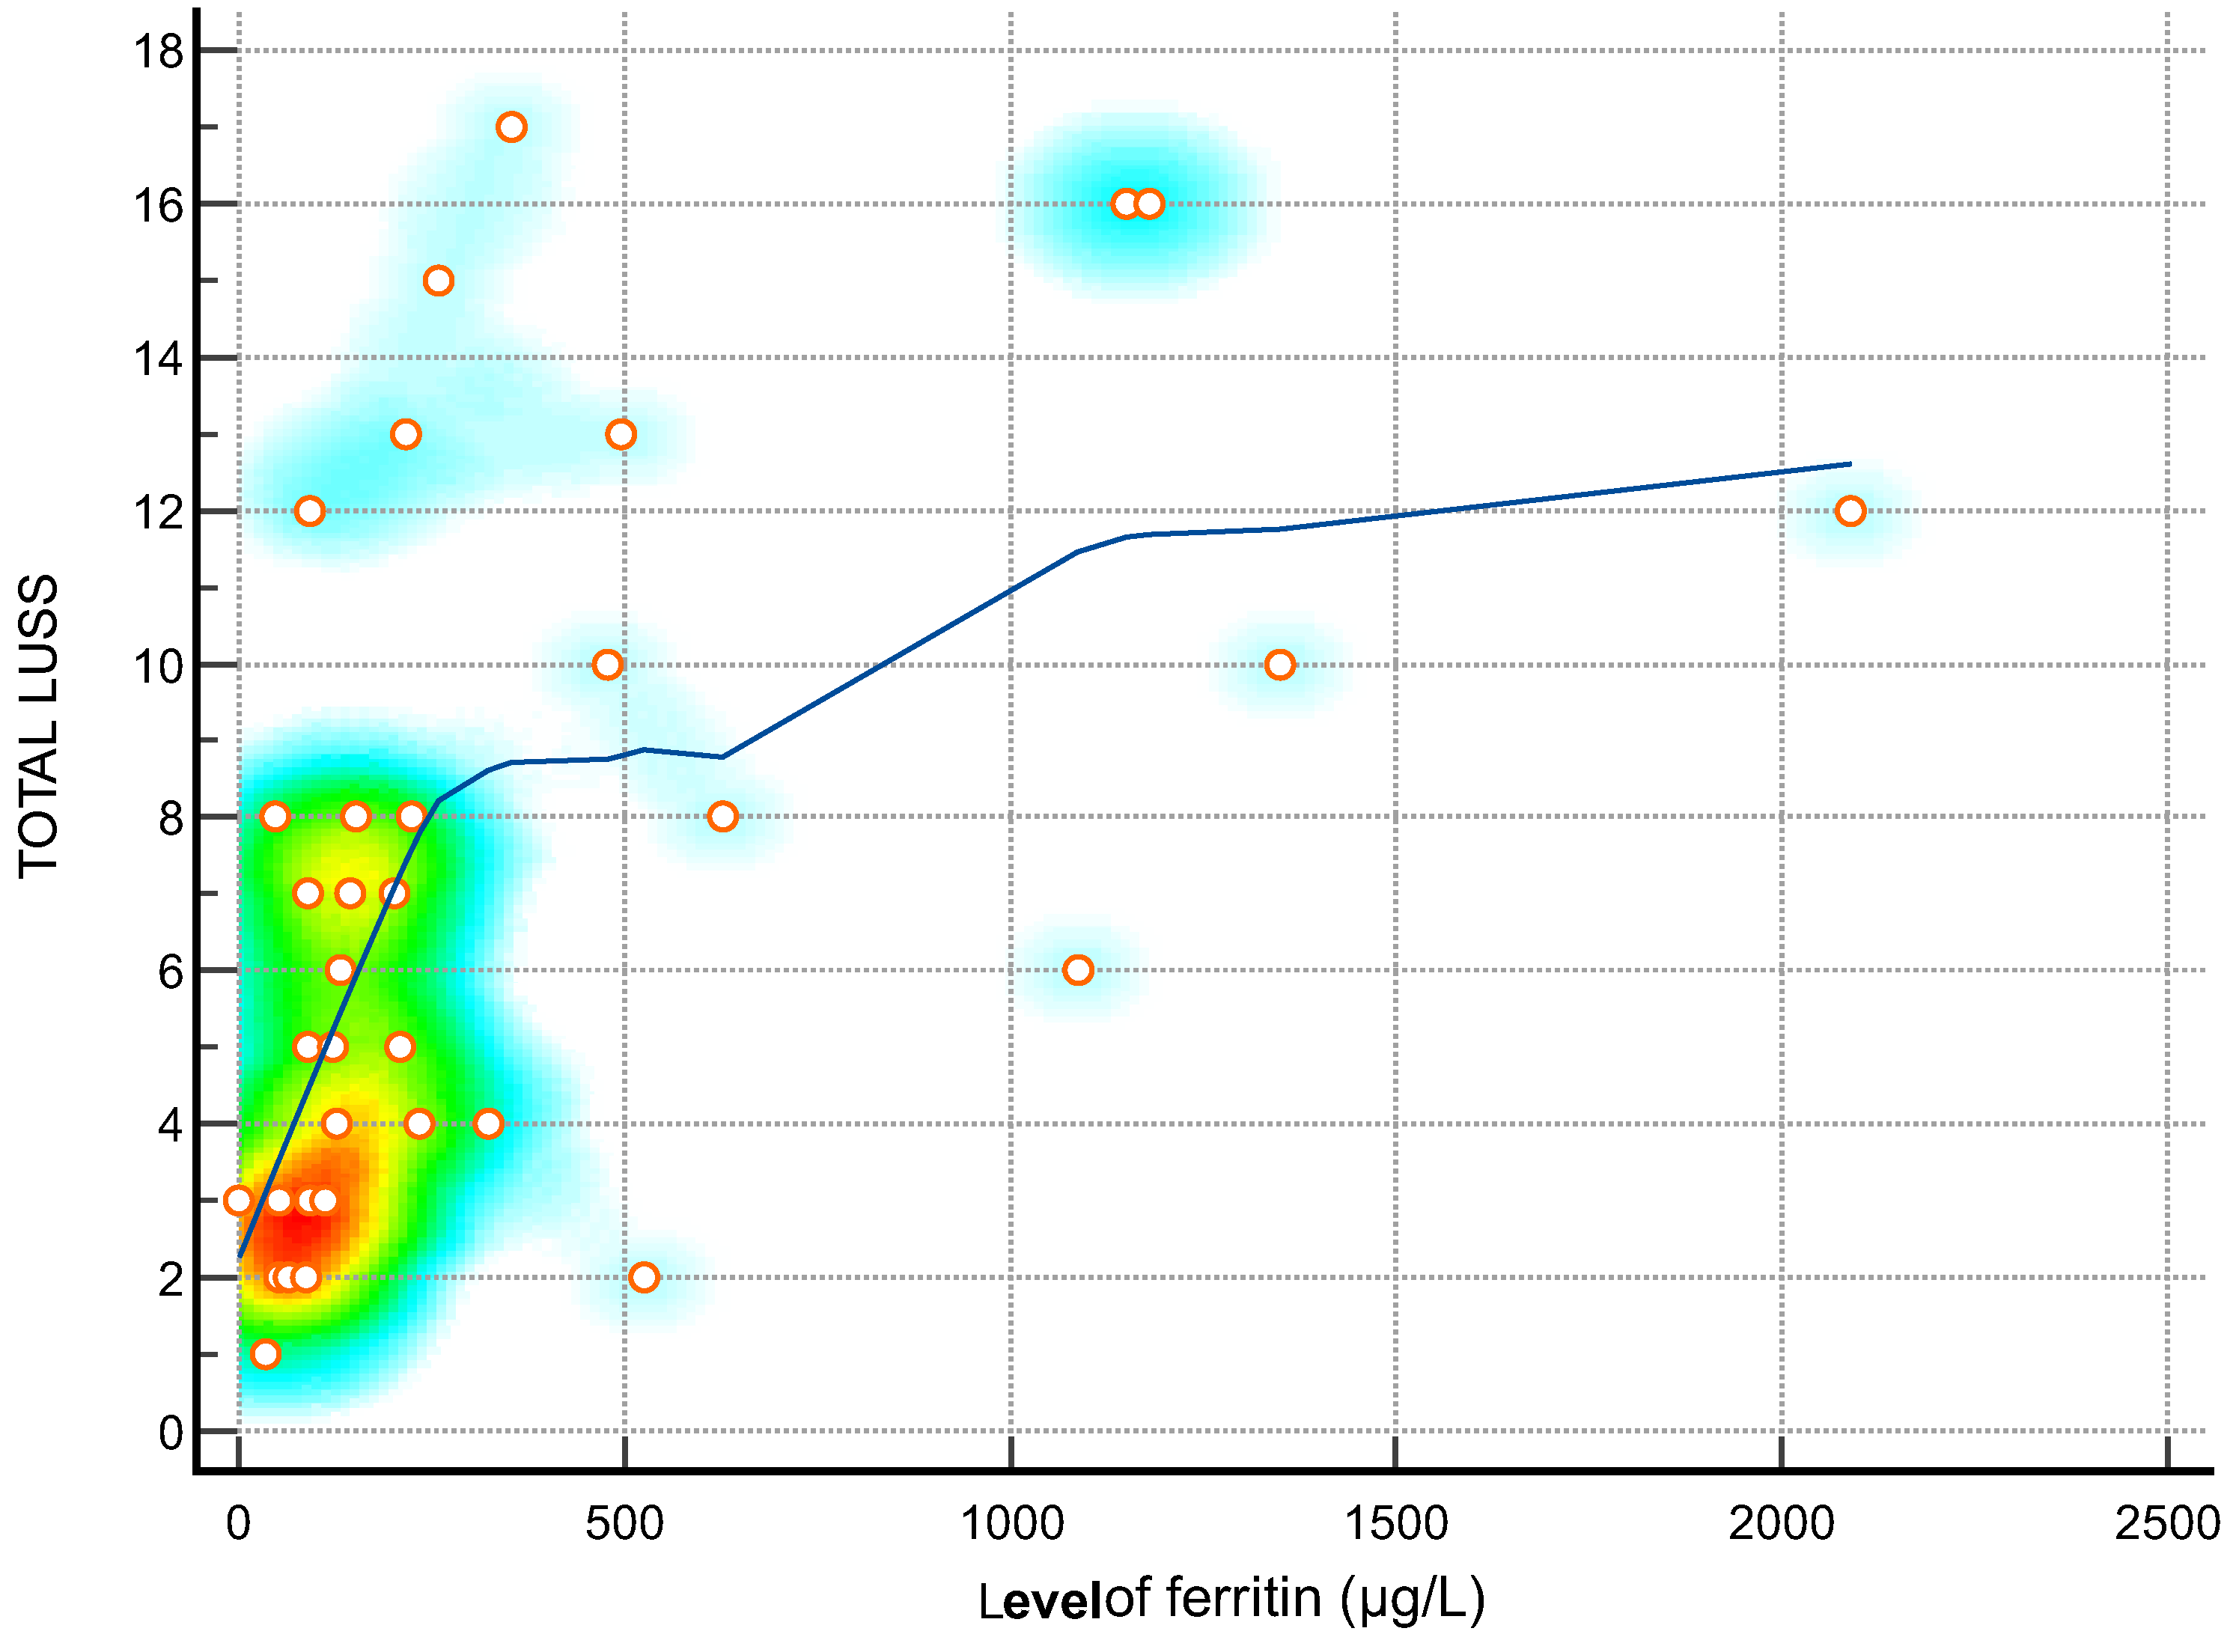

| Ferritin (µg/L)—Figure 2 | 0.62 | 0.36 to 0.79 | 0.0001 |

3.4. Lung Ultrasound Score and Correlation with Inflammatory Markers